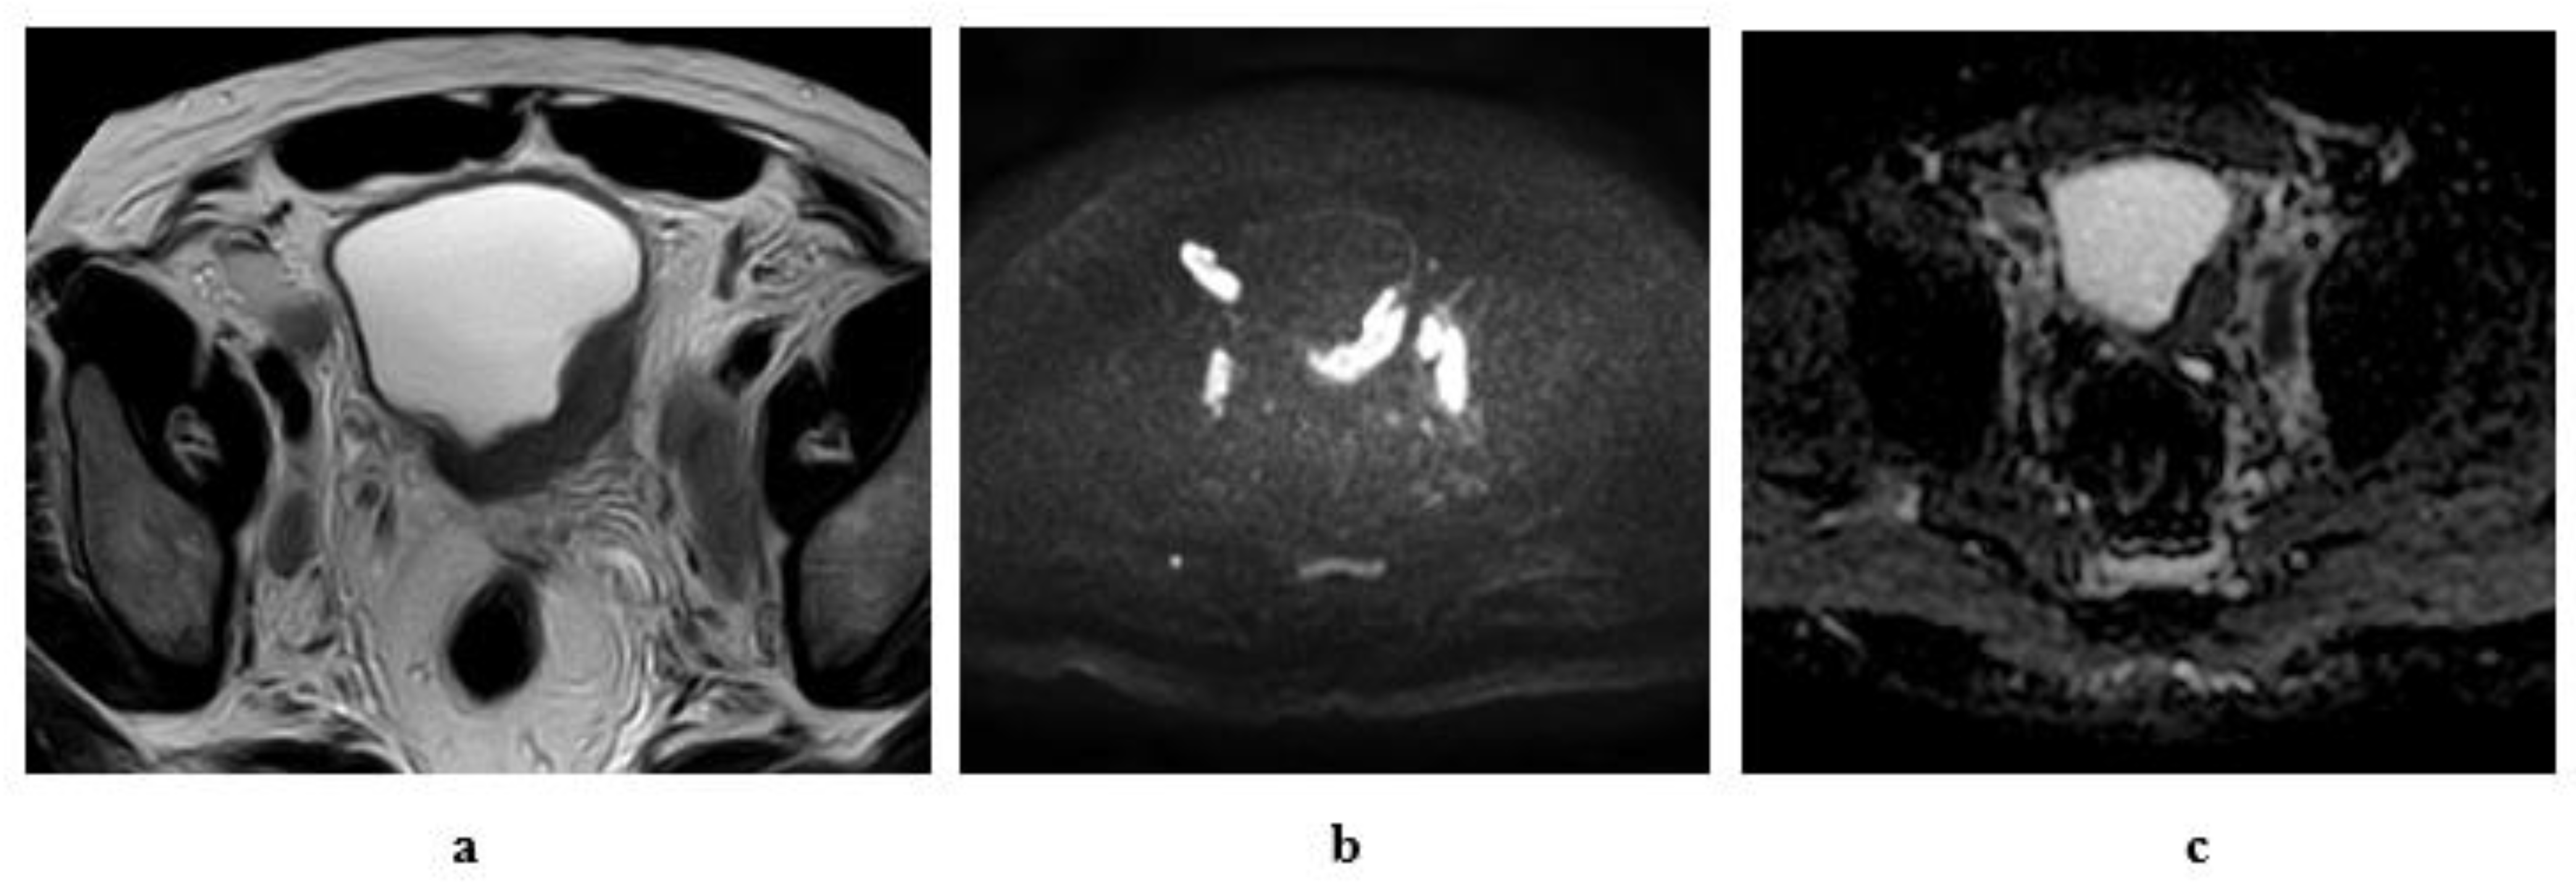

2.6.1. High-Resolution T2-Weighted Imaging (T2WI)

2.6.2. Diffusion-Weighted Imaging (DWI)

2.6.3. Dynamic Contrast-Enhanced (DCE) Imaging

- Stage T1: Intact muscle layer adjacent to the tumor and displays hypointense SI at high resolution T2W sequence without early enhancement on dynamic study.

- Stage T2: Interrupted hypointense line of the muscle layer with early enhancement of the tumor with no extravesical fat invasion.

- Stage T3: irregular outer boundary of the tumor with distortion of the extravesical fat with the same SI of the tumor.

- Stage T4: Tumor infiltrates the surrounding organs or pelvic walls.